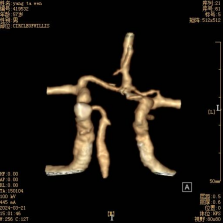

術(shù)前頭顱CTA提示:前交通動(dòng)脈瘤,前交通動(dòng)脈復合體不規則膨大,有多個(gè)囊狀分葉(如箭頭所示)

術(shù)后頭顱CTA提示:前交通動(dòng)脈瘤未顯示(如箭頭所示),雙側大腦前動(dòng)脈A1、A2段及前交通動(dòng)脈動(dòng)脈復合體通暢。